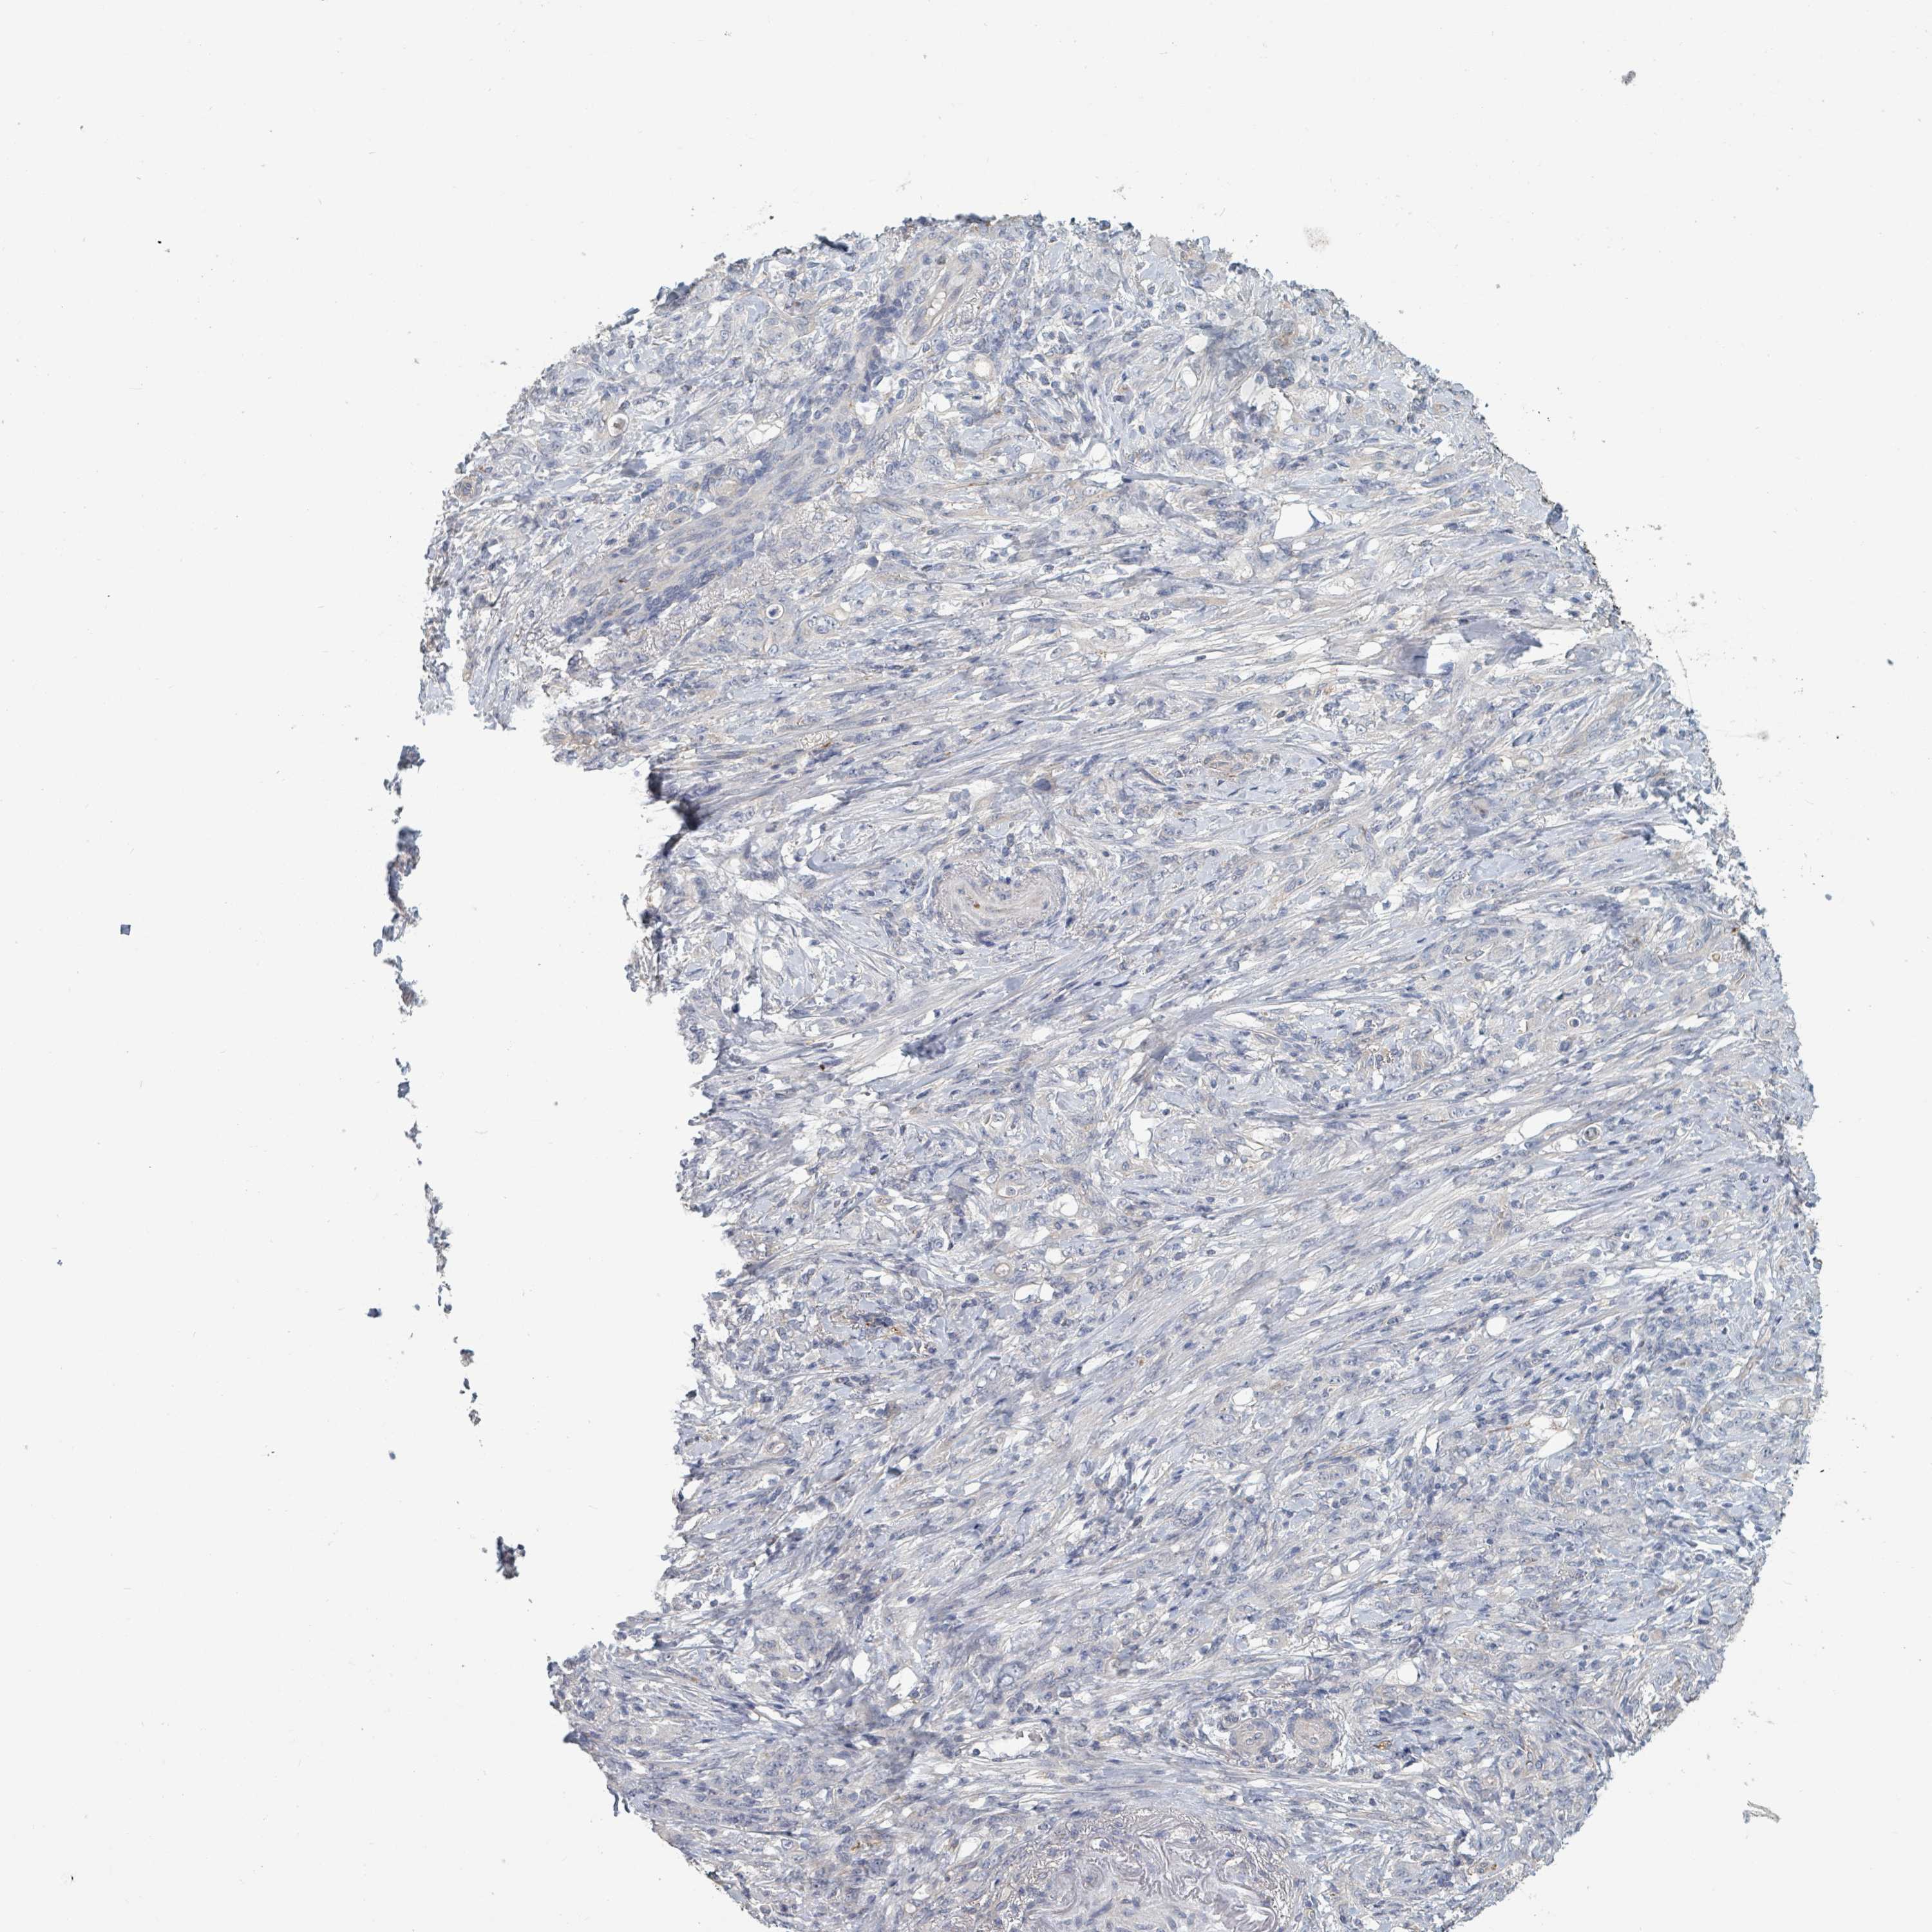

STOMACH CANCER - Protein expressioni

A mouse-over function shows sample information and annotation data. Click on an image to view it in a full screen mode. Samples can be filtered based on level of antibody staining by selecting one or several of the following categories: high, medium, low and not detected. The assay and annotation is described here.

Antibody stainingi

Antibody staining in the annotated cell types in the current human tissue is reported as not detected, low, medium, or high, based on conventional immunohistochemistry profiling in selected tissues. This score is based on the combination of the staining intensity and fraction of stained cells.

Each image is clickable and will lead to virtual microscopy that enables deeper exploration of all samples and also displays staining intensity scores, fraction scores and subcellular localization as well as patient and tissue information for each sample.

Antibody HPA050843

Staining

High

Medium

Low

Not detected

Intensity

Strong

Moderate

Weak

Negative

Quantity

>75%

75%-25%

<25%

None

Location

Nuclear

Cytoplasmic/membranous

Cytoplasmic/membranous,nuclear

Adenocarcinoma, NOS